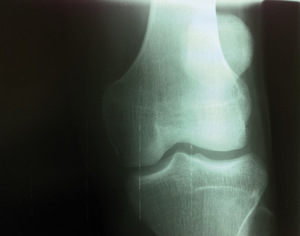

W części udowo-piszczelowej uszkodzenia dotyczą więzadeł pobocznych piszczelowych, łąkotek i obrażeń chrząstki stawowej. Natomiast w części rzepkowo-udowej przy mechanizmach powodujących zwiększenie przyparcia rzepki do powierzchni rzepkowej uda występują zespoły bocznego przyparcia rzepki, przeciążeniowe rozmiękanie chrząstki oraz nawykowe podwichnięcia i zwichnięcia rzepki, które stwierdzamy zwykle w kolanach z wadami rozwojowymi (na podłożu dysplastycznym) oraz przy nieprawidłowej osi kolana w kierunku koślawości (fot. 1, 2).

Przy skręceniu I stopnia bolesne są przyczepy więzadeł pobocznych bez objawów niestabilności. Zakres ruchów nie jest ograniczony. Kolano jest bez wysięku. Natomiast przy mechanizmie powodującym nagłe przyparcie rzepki (zeskok, nagły przysiad, niektóre obciążenia na siłowni) ból przedniego przedziału kolana może wystąpić dopiero po kilku godzinach. Wówczas kolano jest również bez wysięku, ból odczuwa się w czasie chodzenia po schodach (głównie podczas schodzenia), także przy wykonywaniu przysiadów. Podczas czynnego zginania i prostowania kolana jest wyczuwalne, a czasem słyszalne, tarcie i trzeszczenie pod rzepką. W takich przypadkach należy ograniczyć (niekiedy przerwać) na okres ok. dwóch tygodni aktywność rekreacyjną. W badaniu obrazowym na typowych zdjęciach RTG nie widać żadnych zmian.

W rekreacji fizycznej u osób młodych występują one rzadziej niż w sportach zawodowych. Dochodzi do nich podczas nagłych skręceń kolana przy ustabilizowanej stopie. U osób starszych diagnozujemy je częściej i mają one charakter uszkodzeń zwyrodnieniowych. Uszkodzona łąkotka powoduje ból przy ruchach skrętnych ugiętego kolana. Może dawać poczucie bolesnego przeskakiwania, do blokowania włącznie. W urazach tych często występują wysięki. Na typowych radiogramach w uszkodzeniach przewlekłych może być widoczne zwężenie szczeliny stawowej po stronie urazu. Badanie USG, a szczególnie rezonans magnetyczny, uwidacznia więcej szczegółów. Leczenie artroskopowe, w zależności od rodzaju problemu, polega na usunięciu uszkodzonego fragmentu (częściowa meniscectomia) lub zeszyciu (fot. 3). Całkowite wycięcie wykonuje się w wyjątkowych przypadkach, ponieważ w kolanie bez łąkotek szybciej narastają zmiany zwyrodnieniowe. Po częściowym wycięciu łąkotki powrót do sprawności przedoperacyjnej może nastąpić po ok. dwóch tygodniach, natomiast po zeszyciu przerwa, nawet w rekreacji sportowej, wynosi trzy-cztery miesiące.